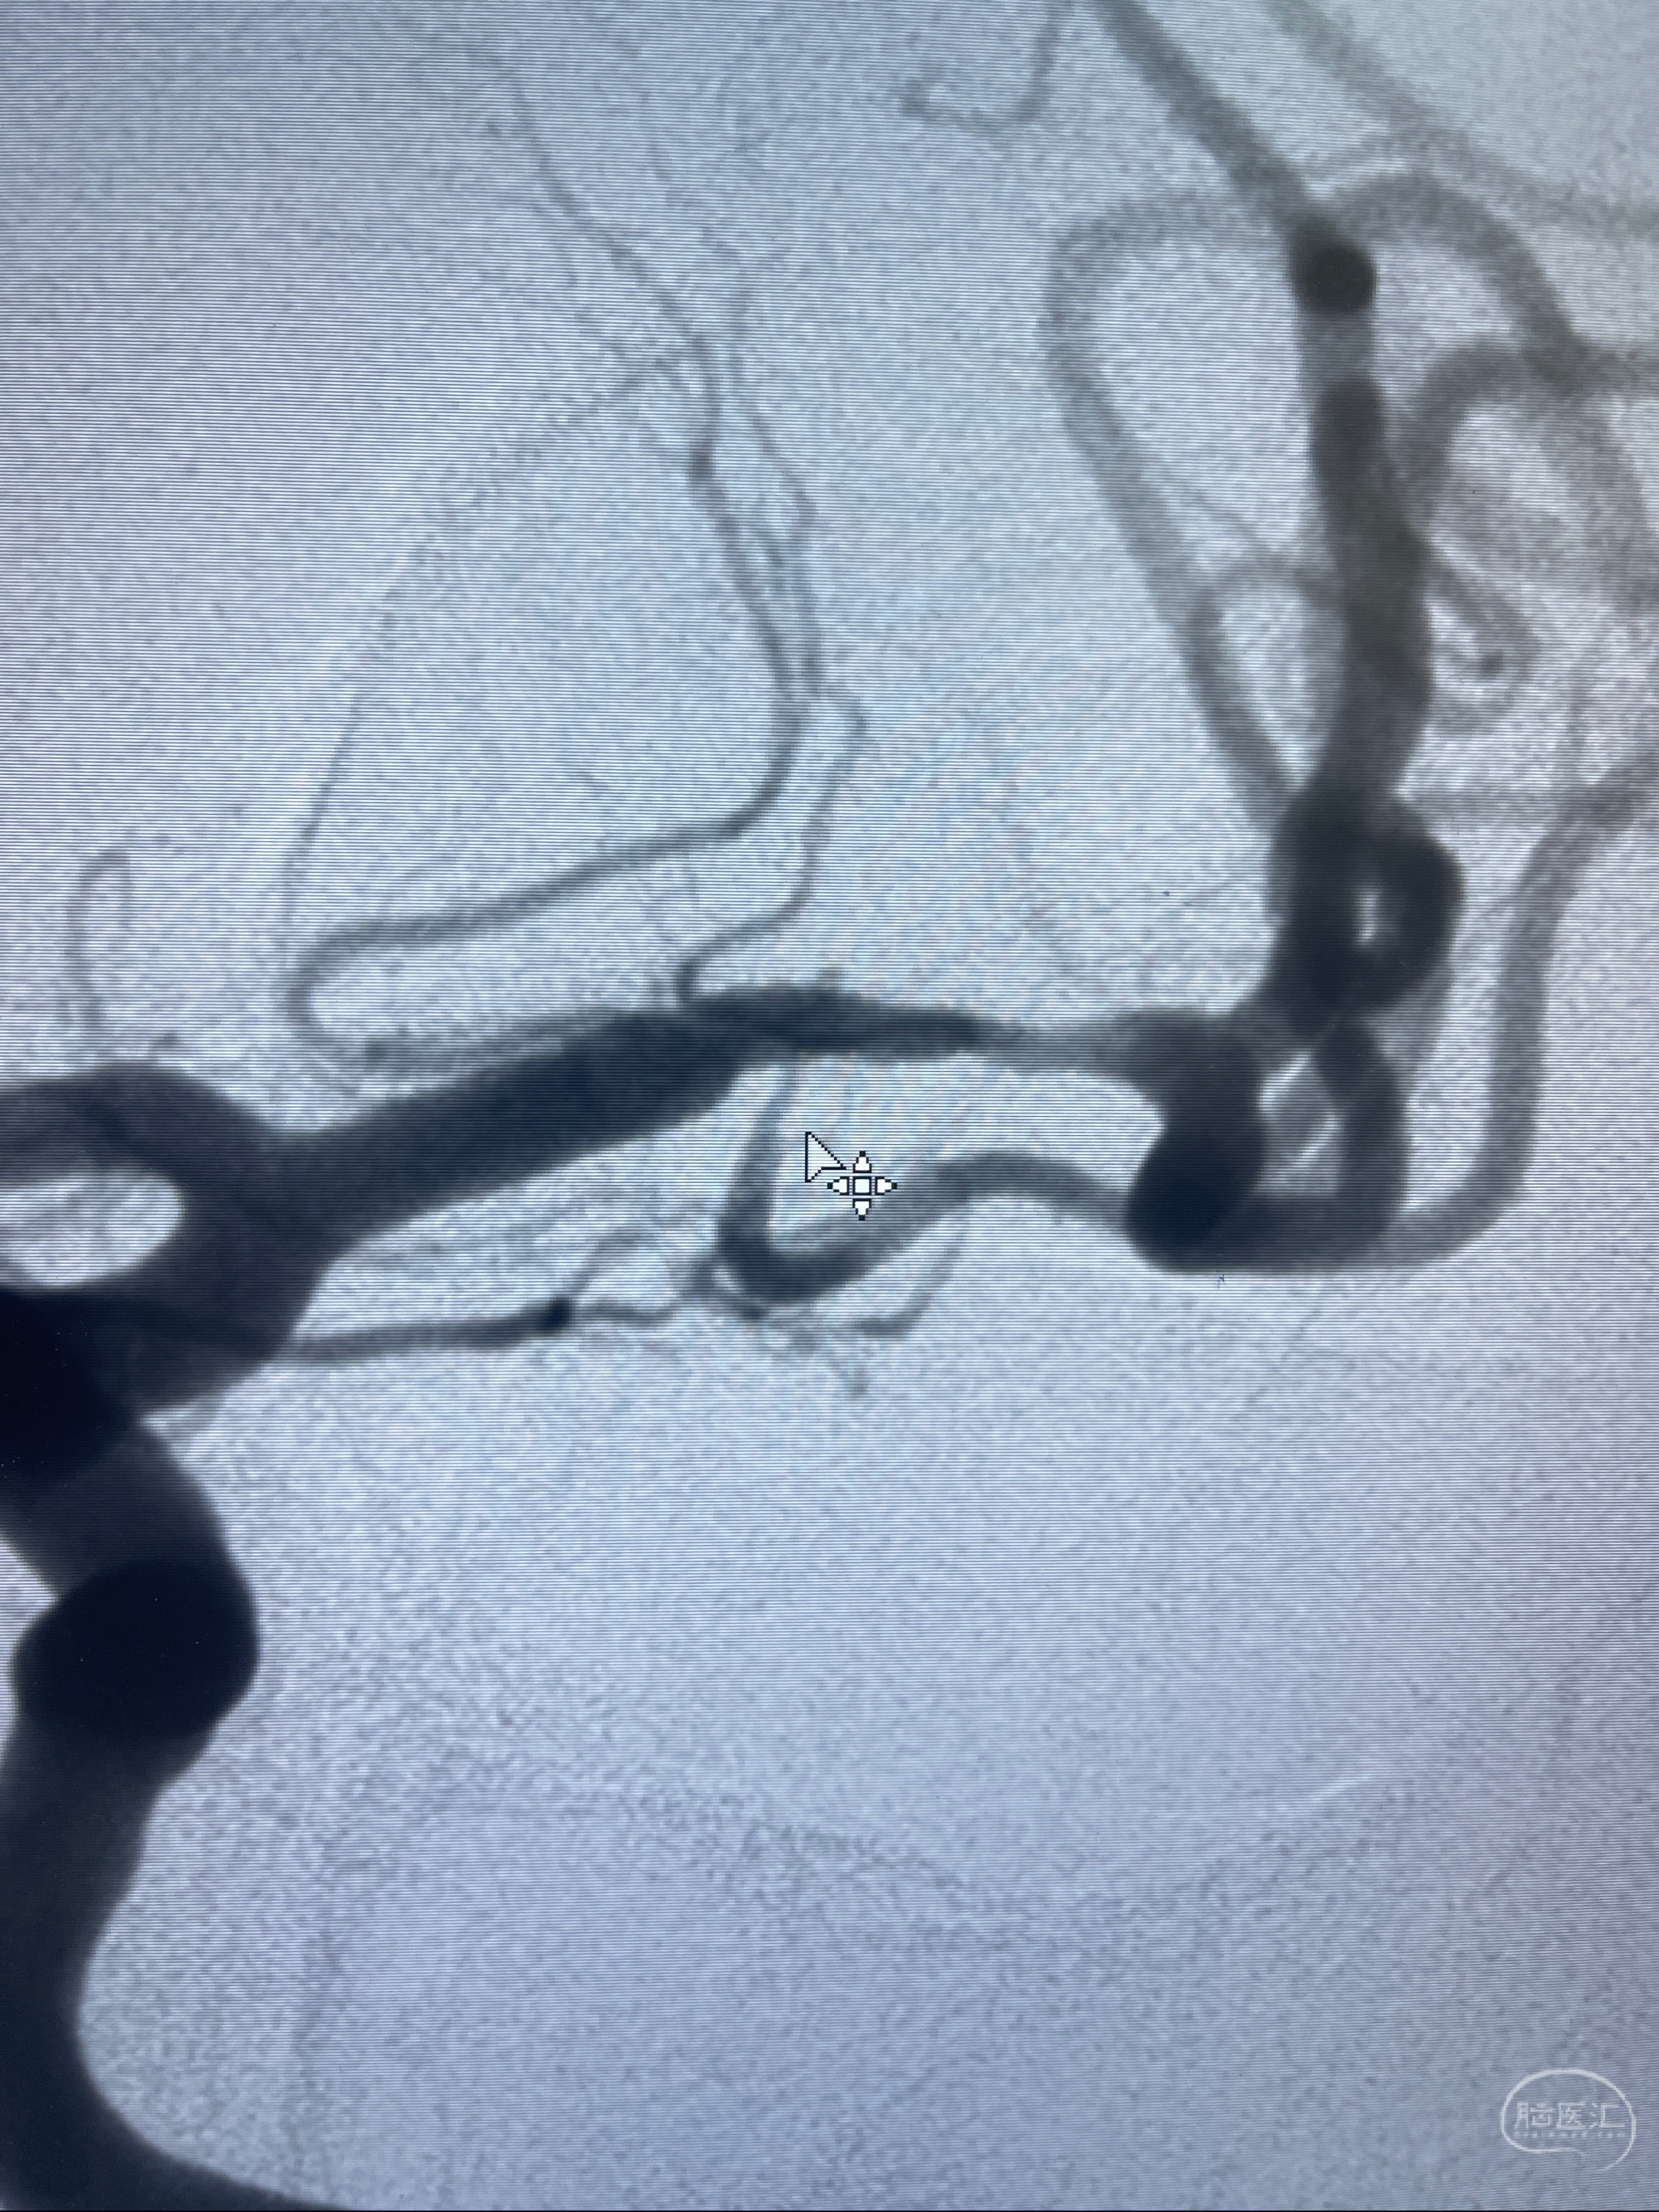

2023-02-15DSA